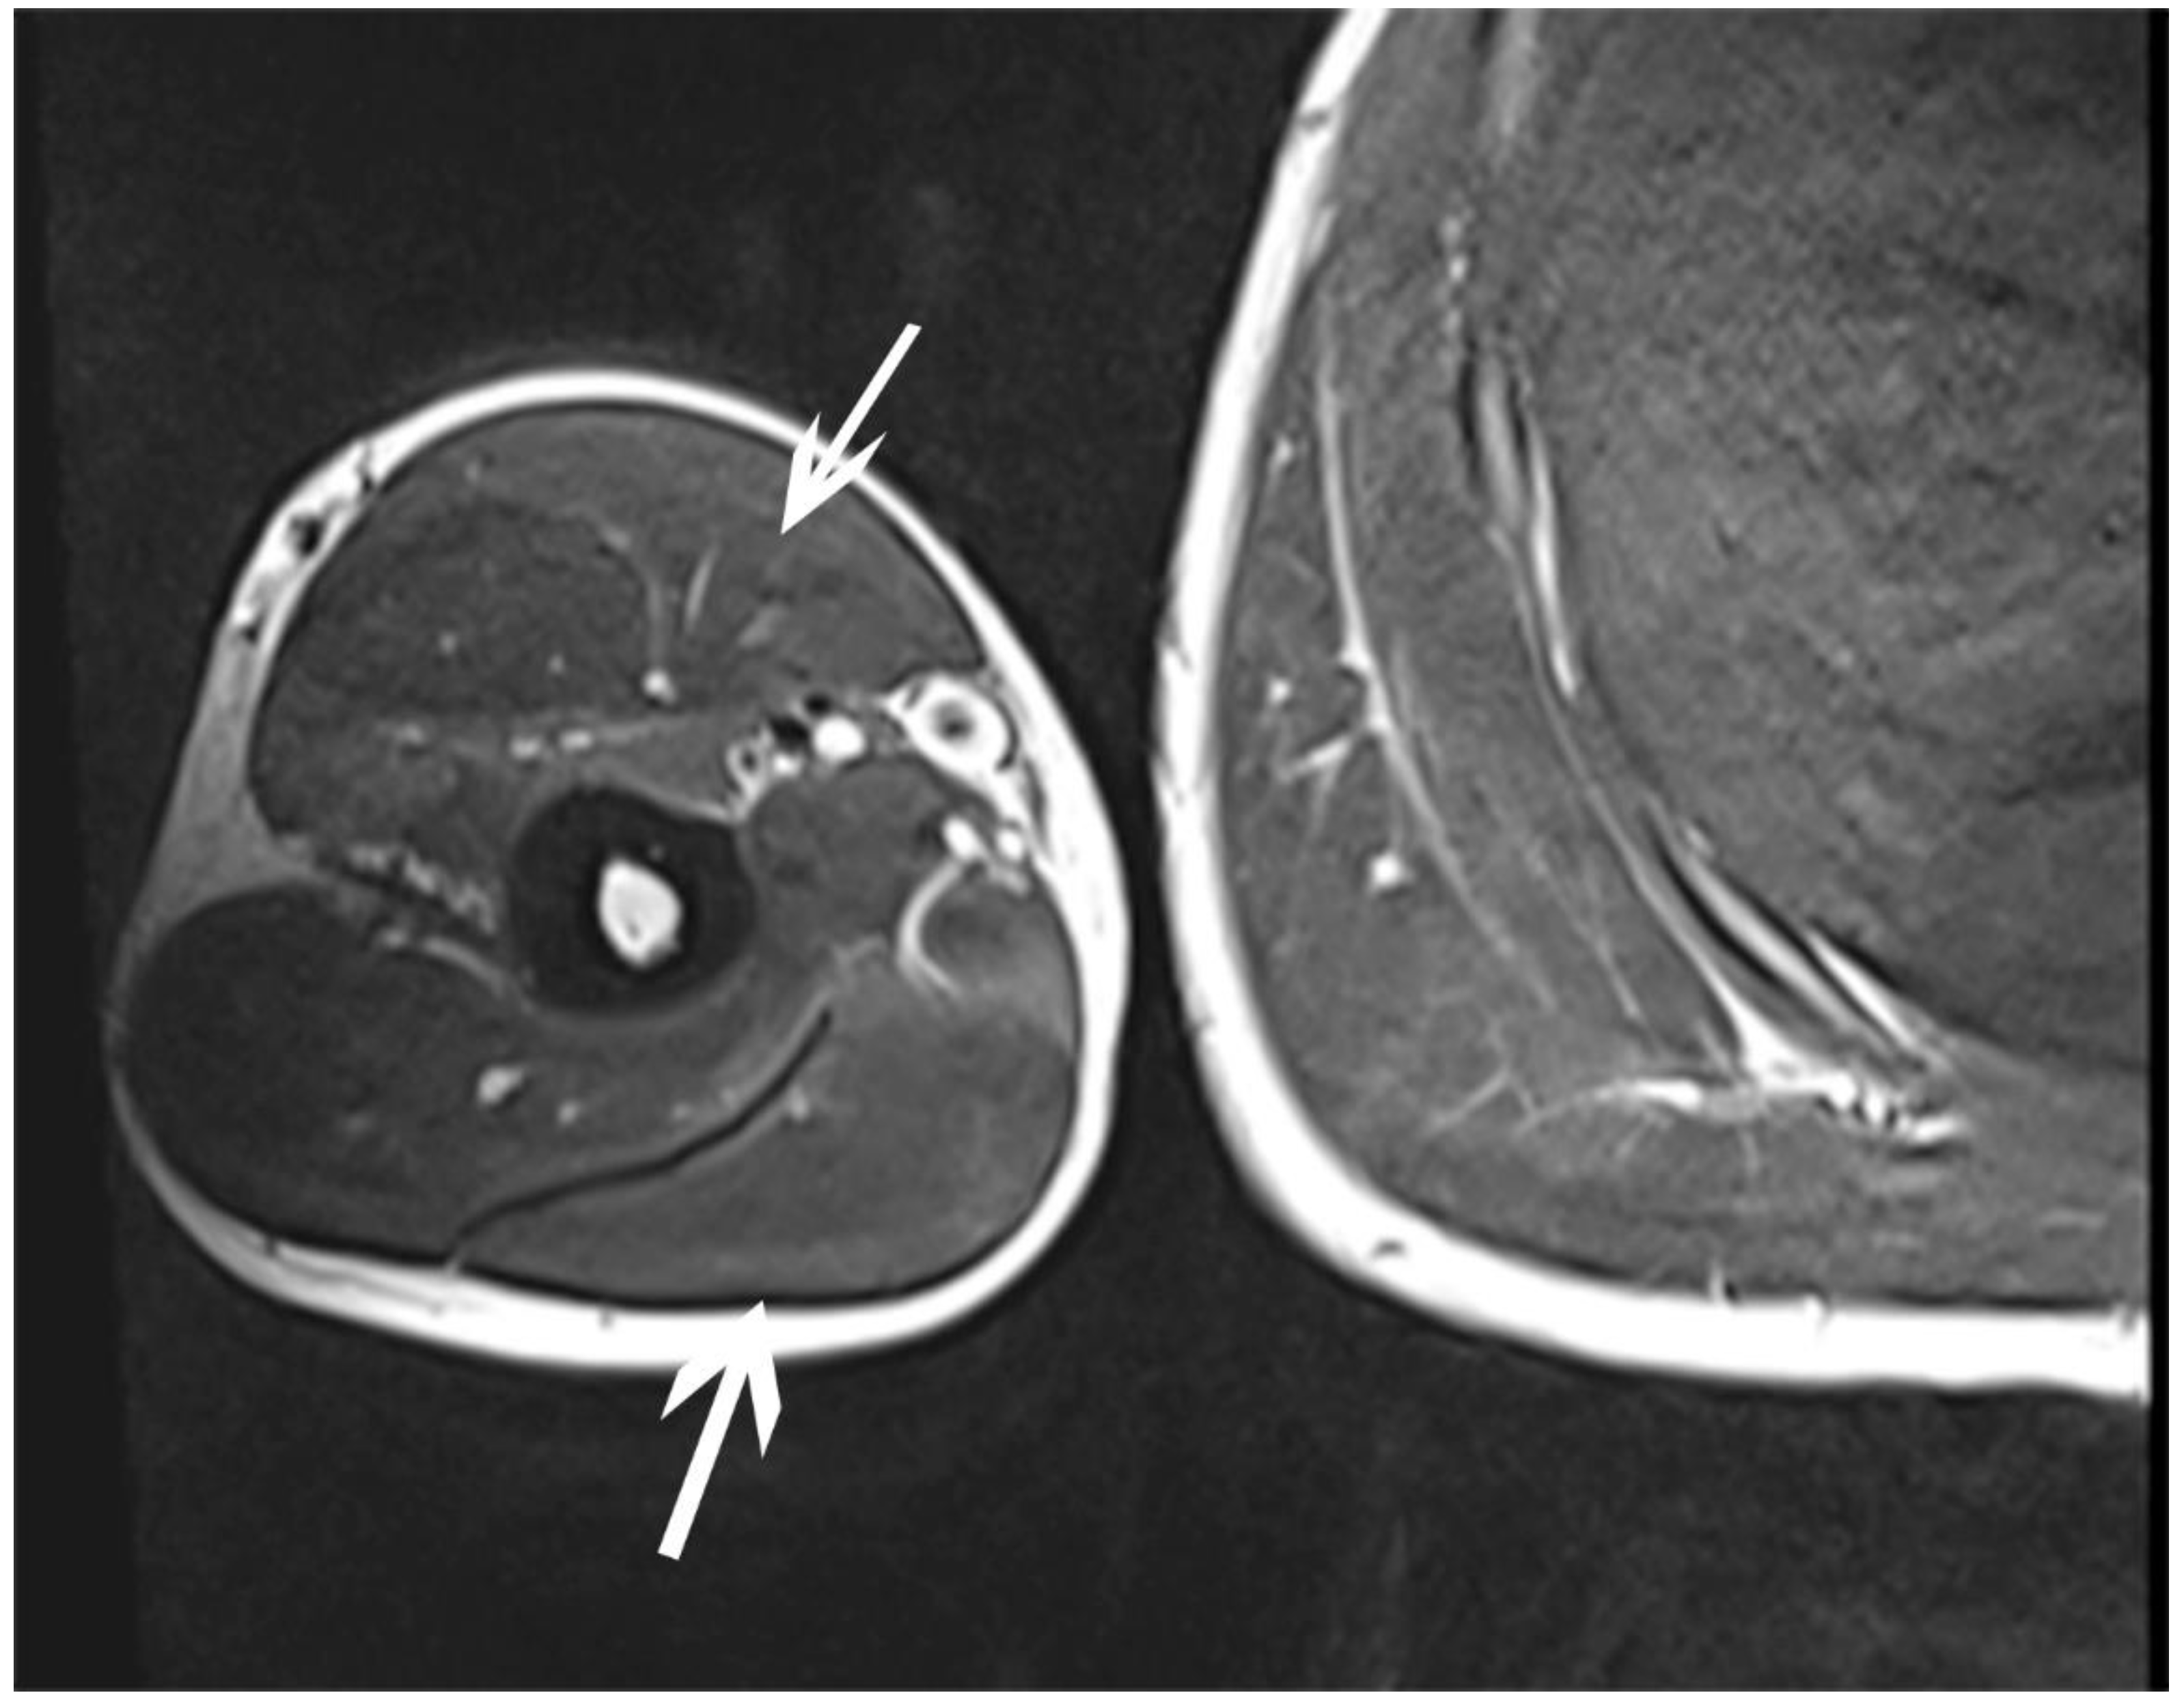

| July | Symptoms: brachialis muscle atrophy (Figure 1 and Figure 2) (pain 4/10 NPRS). Assessment: medical history, physical examination, ultrasound (orthopaedic surgeon). Diagnosis: unspecified soft tissue diseases associated with their use overload and overexertion (M70.9 ICD). Treatment: pharmacological treatment, avoid full weight-bearing. Effects: no positive therapeutic effect. |

| October | Symptoms: episodic of more severe pain, paraesthesia, tingling, numbness and burning sensations of right upper limb, (pain 3/10 NPRS). Assessment: medical history, physical examination (another orthopaedic surgeon), shoulder (Figure 3) and elbow MRI order (the same orthopaedic surgeon), cervical spine MRI order, electromyography, nerve conduction study (Table 2 and Table 3) (another orthopaedic surgeon), medical history, physical examination, ultrasound (another physiotherapist). Diagnosis: mononeuropathy of the upper limb, unspecified (G56.9 ICD) (orthopaedic surgeon), PTS suggestion (physiotherapist) Treatment: orthopedy surgeon: physiotherapy (massage, muscle relaxation, electrostimulation, exercises); physiotherapist recommendation: neurodynamic techniques. Effects: no positive effect. |